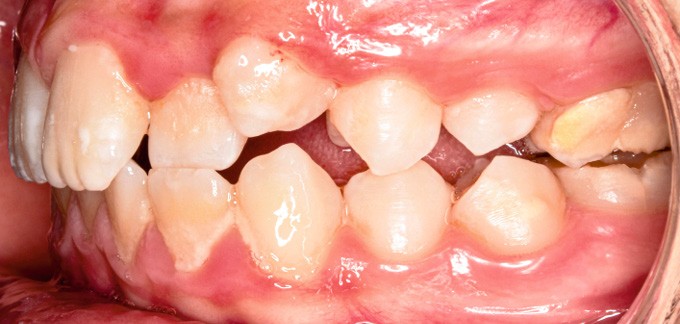

Sur le plan alvéolo-dentaire (fig. 1b) :

- Classe II subdivision gauche avec déviation du point inter-incisif mandibulaire à gauche ;

- occlusion inversée entre 22 et 32 ;

- dysharmonie dento-arcade (DDA) sévère ;

- 13 en position haute retenue.

Sur le plan squelettique : Classe II, schéma hypodivergent (fig. 1c). Sur le plan fonctionnel : aucune dysfonction ni parafonction.